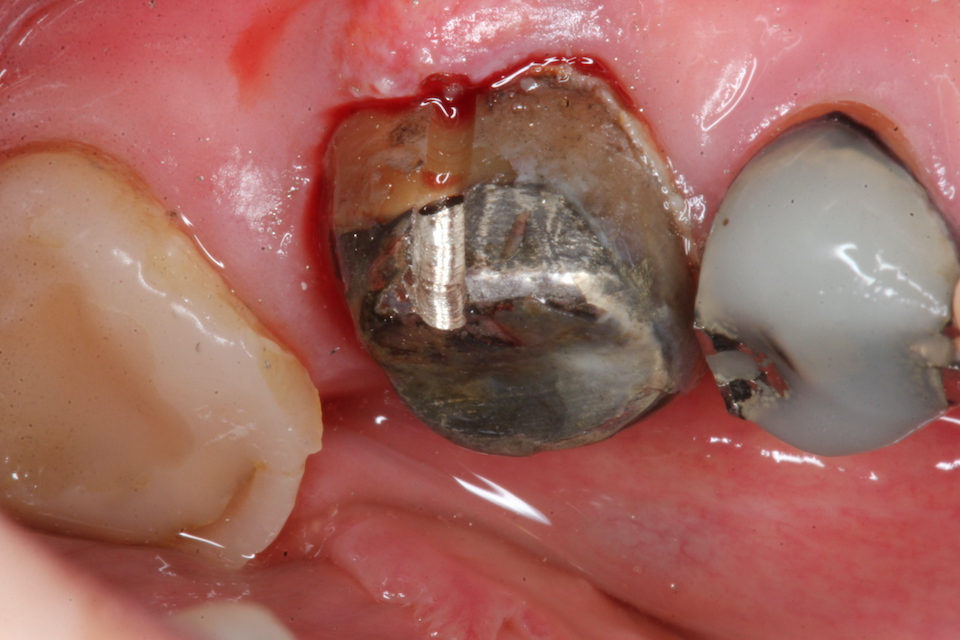

今日の抜歯再植術シリーズ39.1 2025.11.14